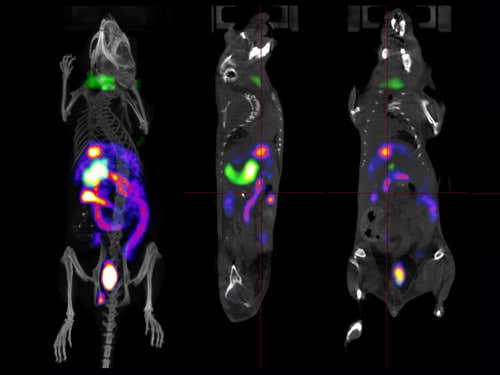

Multitasking scanner

Researchers can track multiple biological processes at once using a dual nuclear imaging scanner that can monitor several radioactive compounds. Each colour pictured corresponds to a different isotope, which indicates the mouse’s metabolism. The purple and white technetium isotope looks at bowel uptake while the green iodine isotope targets the thyroid and spleen.

(Image: UCL CABI)